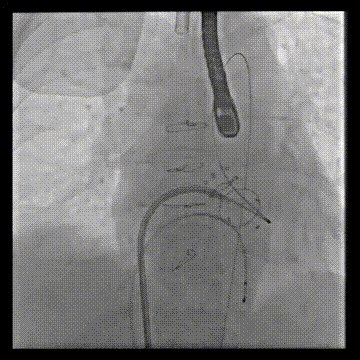

经房间隔二尖瓣跨瓣后,抓捕器在升主动脉抓捕J头泥鳅建立体外化轨道

动脉系统送入7F guiding,将guiding套在JR4导管里面,完成整体导管通路的建立

导管轨道交换Astato 300cm 导丝,确认轨道导丝体外化

将JR4与guiding脱离,guiding头端留在心室,JR导管撤回Agilis可调弯鞘管内